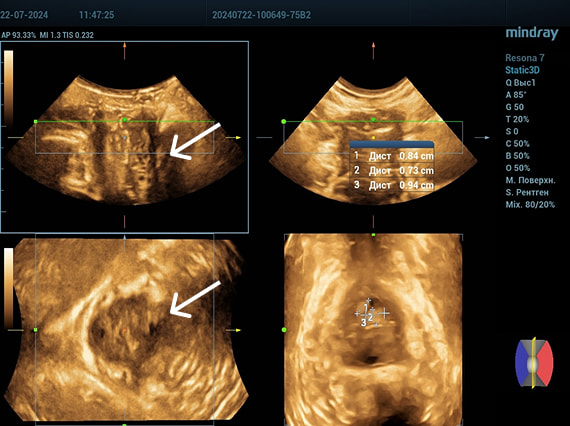

Трансперинеальный доступ, конвексный датчик.

Слева от уретры округлое образование с четкой капсулой и мелкодисперсной взвесью размерами 1,5×1,0 см (филлер с воспалением), справа — анэхогенное овоидное образование (филлер).

Эхограмма 3